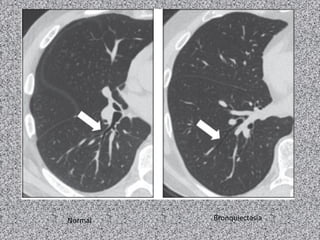

Normal   Bronquiectasia

Bronquiectasia varicosa   Bronquiectasia cística

Tipos de bronquiectasias

a) Cilíndrica : padrão morfológico mais comum;

b) Varicosa: aparência serpeginosa e contornos

internos irregulares;

c) Cística: presença de imagens císticas contínuas

com os brônquios principais.